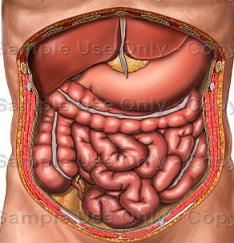

عکس داخل شکم انسان. در این همان طور که مشخص است شکم حالت بیضی شکل پیداکرده و این بیضی که کناره های شکم کشیده شده است. تعداد سلول های بدن انسان حدود ۳۷ ۲ تریلیون تخمین زده شده اند. Abdomen که در زبان عامه به غلط به آن دل نیز می گویند در آناتومی به قسمتی از تنه گفته می شود که مابین دیافراگم از بالا و سطح فوقانی لگن خاصره از پایین قرار دارد. ربات دیدنی ربات انساننمای چینی به صورت یک دختر جوان ساخته شده و جیا جیا نامگذاری شده است این ربات طوری برنامهریزی شده که میتواند صحبت کند و احساسات خود را از طریق تغییرات در چهره حالات.

شکل دوم شکم مادری را نشان می دهد که جنین دختر دارد. وحشت مادر از عکس سونوگرافی جنین داخل شکمش عکس. تصاویر جالب از داخل مغز و نخاع انسان آخرین نیوز. بدن انسان کل ساختار انسان است که سر گردن تنه سینه و شکم دو بازو و دست ها و دو ساق پا و پاها را شامل می شود.